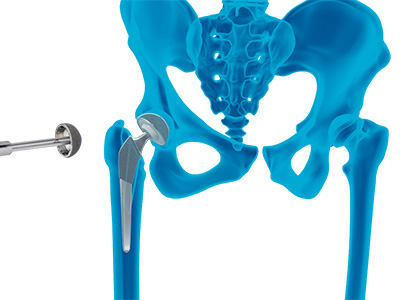

Hip Arthroscopy Anterior Hip Replacement

Anterior Hip Replacement Robotic Assisted Hip Replacement

Robotic Assisted Hip Replacement Total Hip Replacement

Total Hip Replacement Outpatient Hip Replacement